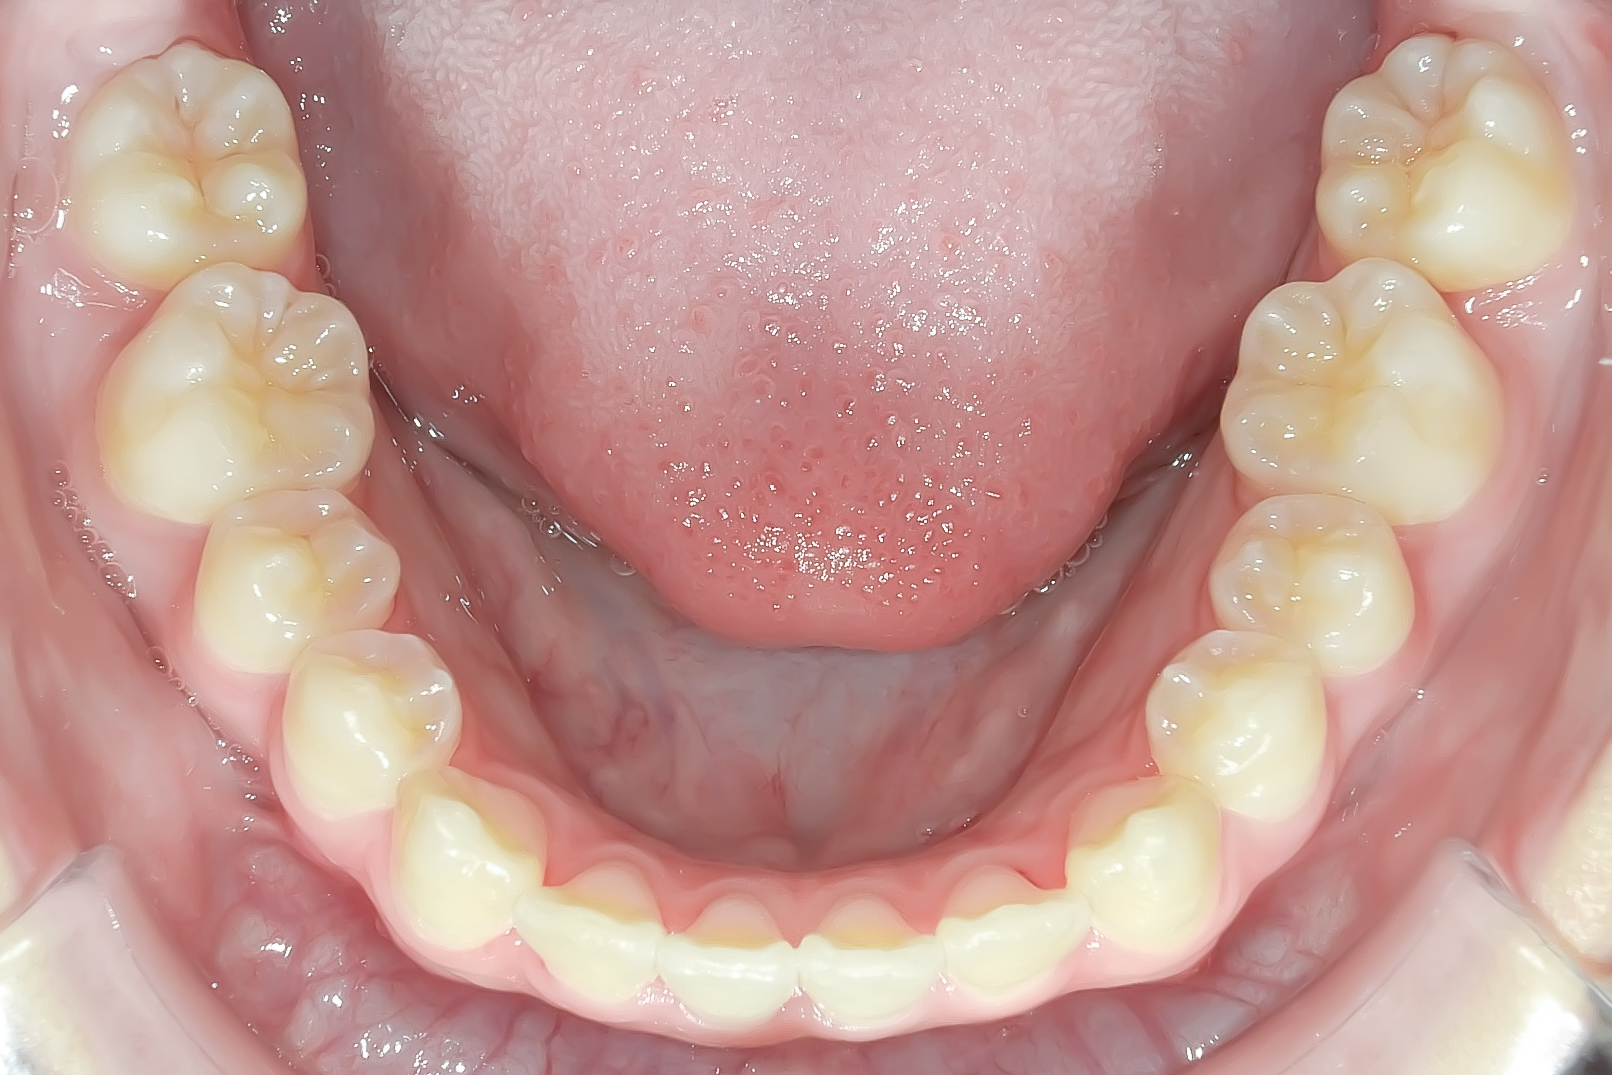

After

治療後です。叢生がなくなりきれいに並んでいます。

下顎も叢生がなくなりました。